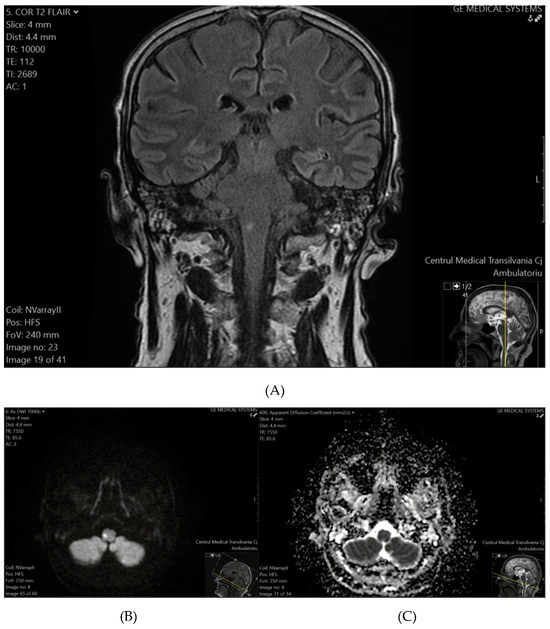

Ischemic lesions were identified in 26.92% of patients (95% CI: 11.6–47.8%), with a higher prevalence observed among older individuals, males, and those with a history of hypertension. These findings suggest that nearly one in four patients in the study cohort showed evidence of ischemic lesions, highlighting the importance of incorporating advanced imaging techniques to detect such lesions and understand their clinical significance in targeted patient subgroups. Representative MRI images from two patients illustrate characteristic ischemic lesions identified in our study cohort (Figure 1 and Figure 2). In Patient 1, a hyperintense lesion was observed in the right medulla oblongata on T2-FLAIR (Figure 1A), with corresponding diffusion restriction on DWI (Figure 1B) and a hypointense ADC signal (Figure 1C), confirming acute ischemia.

Figure 1. (A) (top) T2-FLAIR sequence reveals a hyperintense focus on the right side of the medulla oblongata. (B) (bottom-left) DWI confirms an ischemic event, demonstrating diffusion restriction with a hyperintense signal. (C) (bottom-right) The corresponding ADC map shows a hypointense signal, further supporting the presence of acute ischemia.